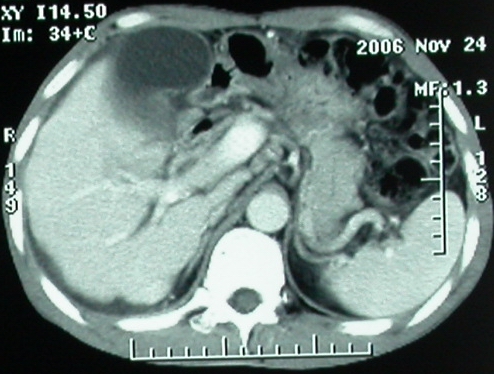

增强ct所见【动脉增强期】

门脉主干及肠系膜上静脉近端明显增粗,尤其前者呈等低混杂密度,增强后周围见轻度环形强化。明显占位效应。肝内外胆管见大量气体影。胆囊明显增大。

考虑:1、门脉栓塞; 2、肝内外胆管积气。

影像表现:胆囊扩张、肝内胆管不扩张,且见肝脏内树枝样气体影;十二指肠后方等密度占位,中心有不规则囊变区。增强实质部分轻度强化。下部腔静脉未强化------有栓子吗?

ct表现:1,胰腺钩突后方肿块,不均强化,中心密度低,钩突及门静脉前移。2:肝右后叶不均强化灶,突出肝表面,3:胆囊明显增大,肝内胆管及肝总管内积气。4:腹腔内少量积液。